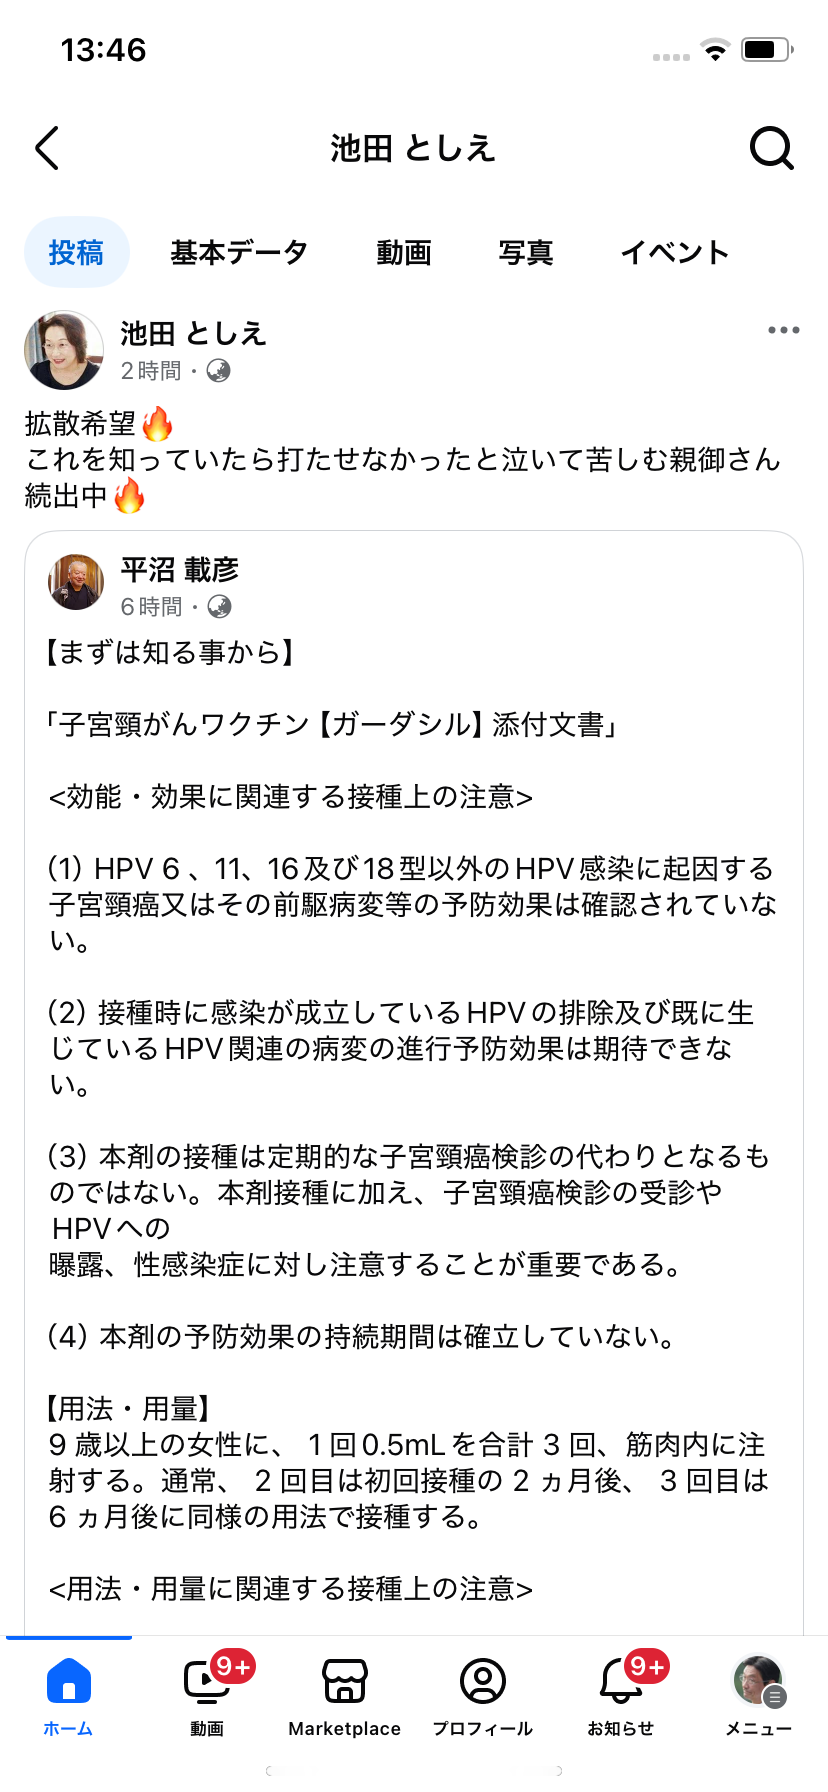

どうする?子宮頸癌ワクチン 出典・フェイスブック

iPhoneから送信

2025.01.21